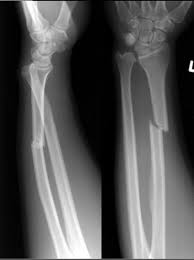

What is the name for this injury?

Galaezzi fracture-dislocation (Distal Radius fx with distal ulnar dislocation)